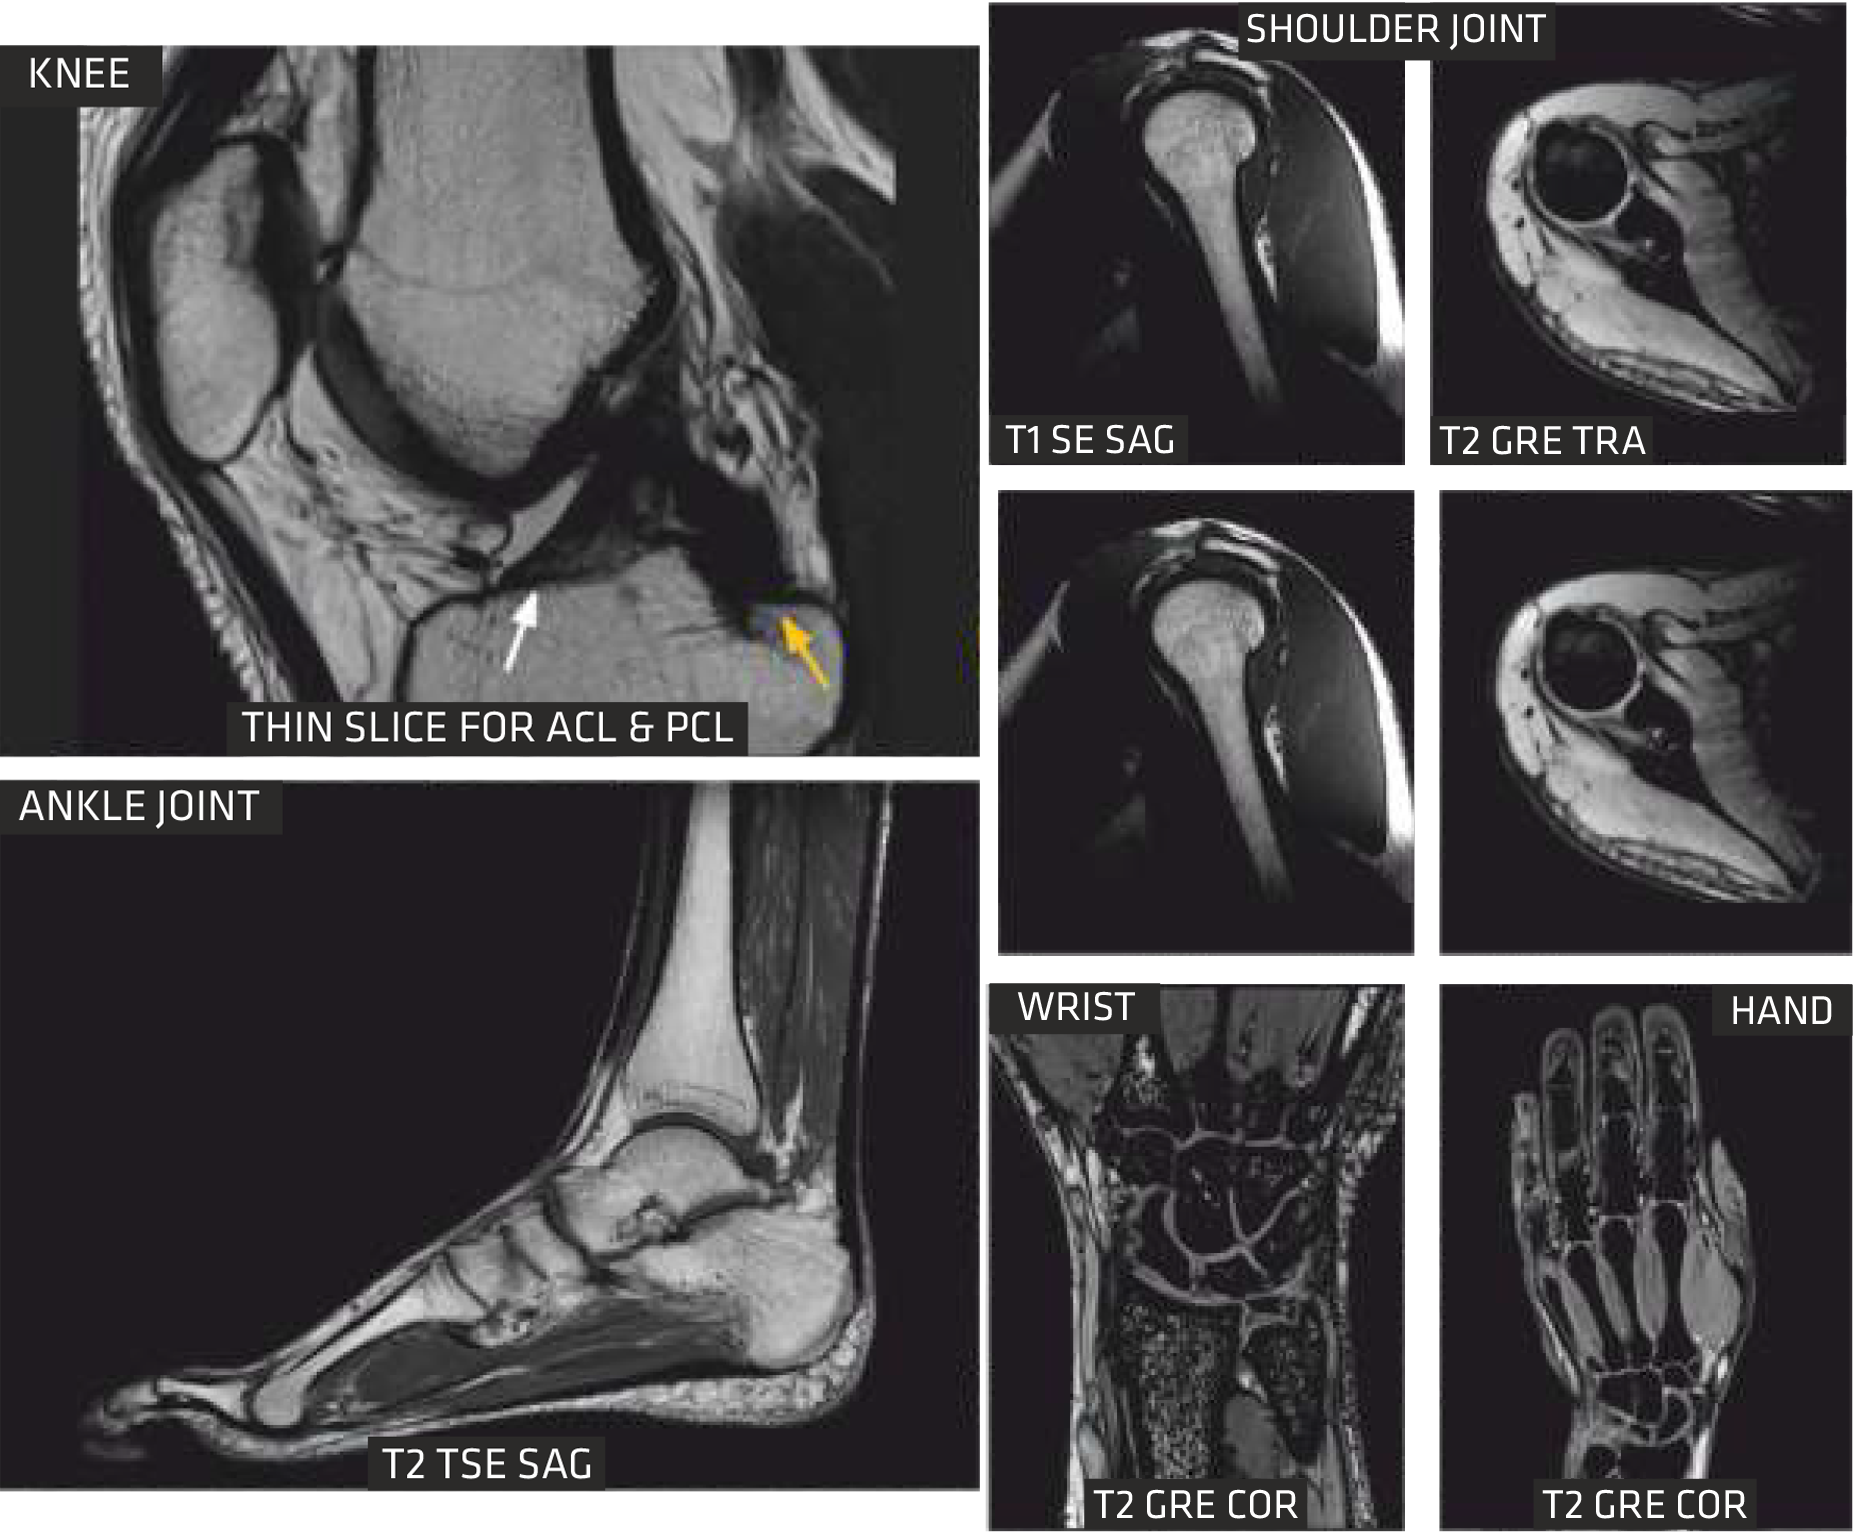

With advancements in MSK sequences, RF coils, computing technology and optimized magnet homogeneity, Clarity delivers high resolution musculoskeletal(MSK) images. This imaging technique enables you to image bone, joint and muscular soft tissue with remarkable tissue contrast.

Cartilage Quantification provides quantitative assessment of cartilage composition to track the degradation of tissues in the early stages of multiple pathologies? within joints, which can't be detected by conventional imaging techniques. It allows for non-invasive measurement of collagen content.